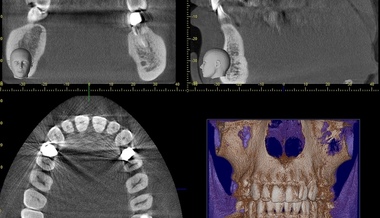

Când examenul clinic nu oferă toate răspunsurile, medicul poate solicita un CT pentru sinusuri. Prin această metodă, vei avea acces la imagini detaliate, în care apar eventualele anomalii la nivelul sinusurilor:

- Blocaje;

- Polipi;

- Acumulări de lichid sau puroi;

- Inflamaţii persistente;

- Rareori, tumori.

Comparativ cu radiografia clasică, un CT pentru sinusuri la MedLife oferă informaţii mult mai precise. Medicul poate astfel să stabilească rapid dacă e nevoie doar de tratament medicamentos sau dacă s-ar putea impune o intervenţie. CT-ul de sinusuri foloseşte o doză mică de radiaţii şi nu implică proceduri invazive, ceea ce îl face o alegere sigură şi eficientă pentru diagnosticul corect al sinusurilor.